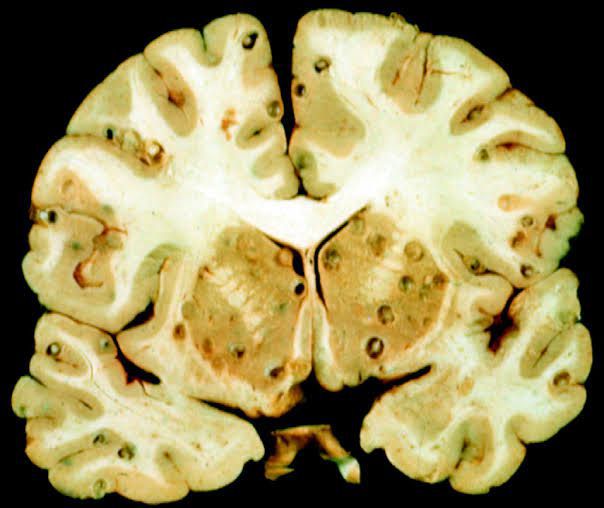

Neurocysticercosis is a preventable parasitic infection caused by larval cysts (enclosed sacs containing the immature stage of a parasite) of the pork tapeworm (Taenia solium). The larval cysts can infect various parts of the body causing a condition known as cysticercosis.